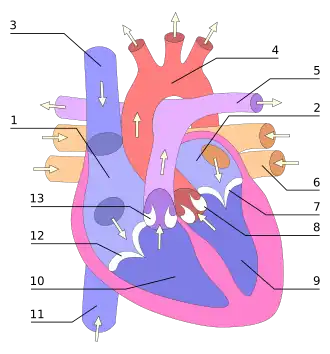

1. Atriu drept;

2. Atriu stâng;

3. Vena cavă superioară;

4. Aorta;

5. Arteră pulmonară;

6. Venă pulmonară;

7. Valva mitrală;

8. Valva aortică;

9. Ventricul stâng;

10. Ventricul drept;

11. Vena cavă inferioară; br> 12. Valva tricuspidiană;

13. Valvă pulmonară.

Inima, în greutate de 350 grame la un adult, are forma unui con cu vârful îndreptat în jos, iar baza corespunde marilor vase (venele cave, artera pulmonară, aorta). Este un organ muscular ai cărui pereți au patru straturi: pericardul - sac fibros în care este adăpostită inima , miocardul (mușchiul inimii), căptușit în interior de endocard, iar la exterior de o membrană seroasă, epicardul.[1] Pompa cardiacă are patru camere: atriul drept și atriul stâng (sau urechiușa dreaptă respectiv stângă) cu pereții subțiri - camerele de primire - și ventriculul drept și ventriculul stâng cu pereții mai groși, care constituie pompa efectivă.[2]

Între cavități există orificii de comunicare și anume: între atriul și ventriculul stâng - valva mitrală, între atriul și ventriculul drept valva tricuspidiană; din ventriculul stâng iese aorta cu valva aortică, iar din ventriculul drept iese artera pulmonară cu valva ei. Buna funcționare a aparatelor valvulare favorizează umplerea cu sânge a inimii în perioada de repaos (diastolă) și propulsarea lui după contracție (sistolă) în marea și mica circulație.[1]

Inima este singurul organ muscular care se contractă ritmic, fără întrerupere, din viața embrionară până la moarte. Automatismul cardiac este asigurat de un centru specializat (nodul sinusal situat în atriul drept), de la care pornește stimulul cardiac și de unde este transmis mai departe de nodulul atrioventricular (situat în septul inter-atrial), apoi de fasciculul His (din septul interventricular) și rețeaua Purkinje (din pereții ventriculari a căror activitate electrică dau undele pozitive și negative pe electrocardiogramă (abreviată EKG).[3]